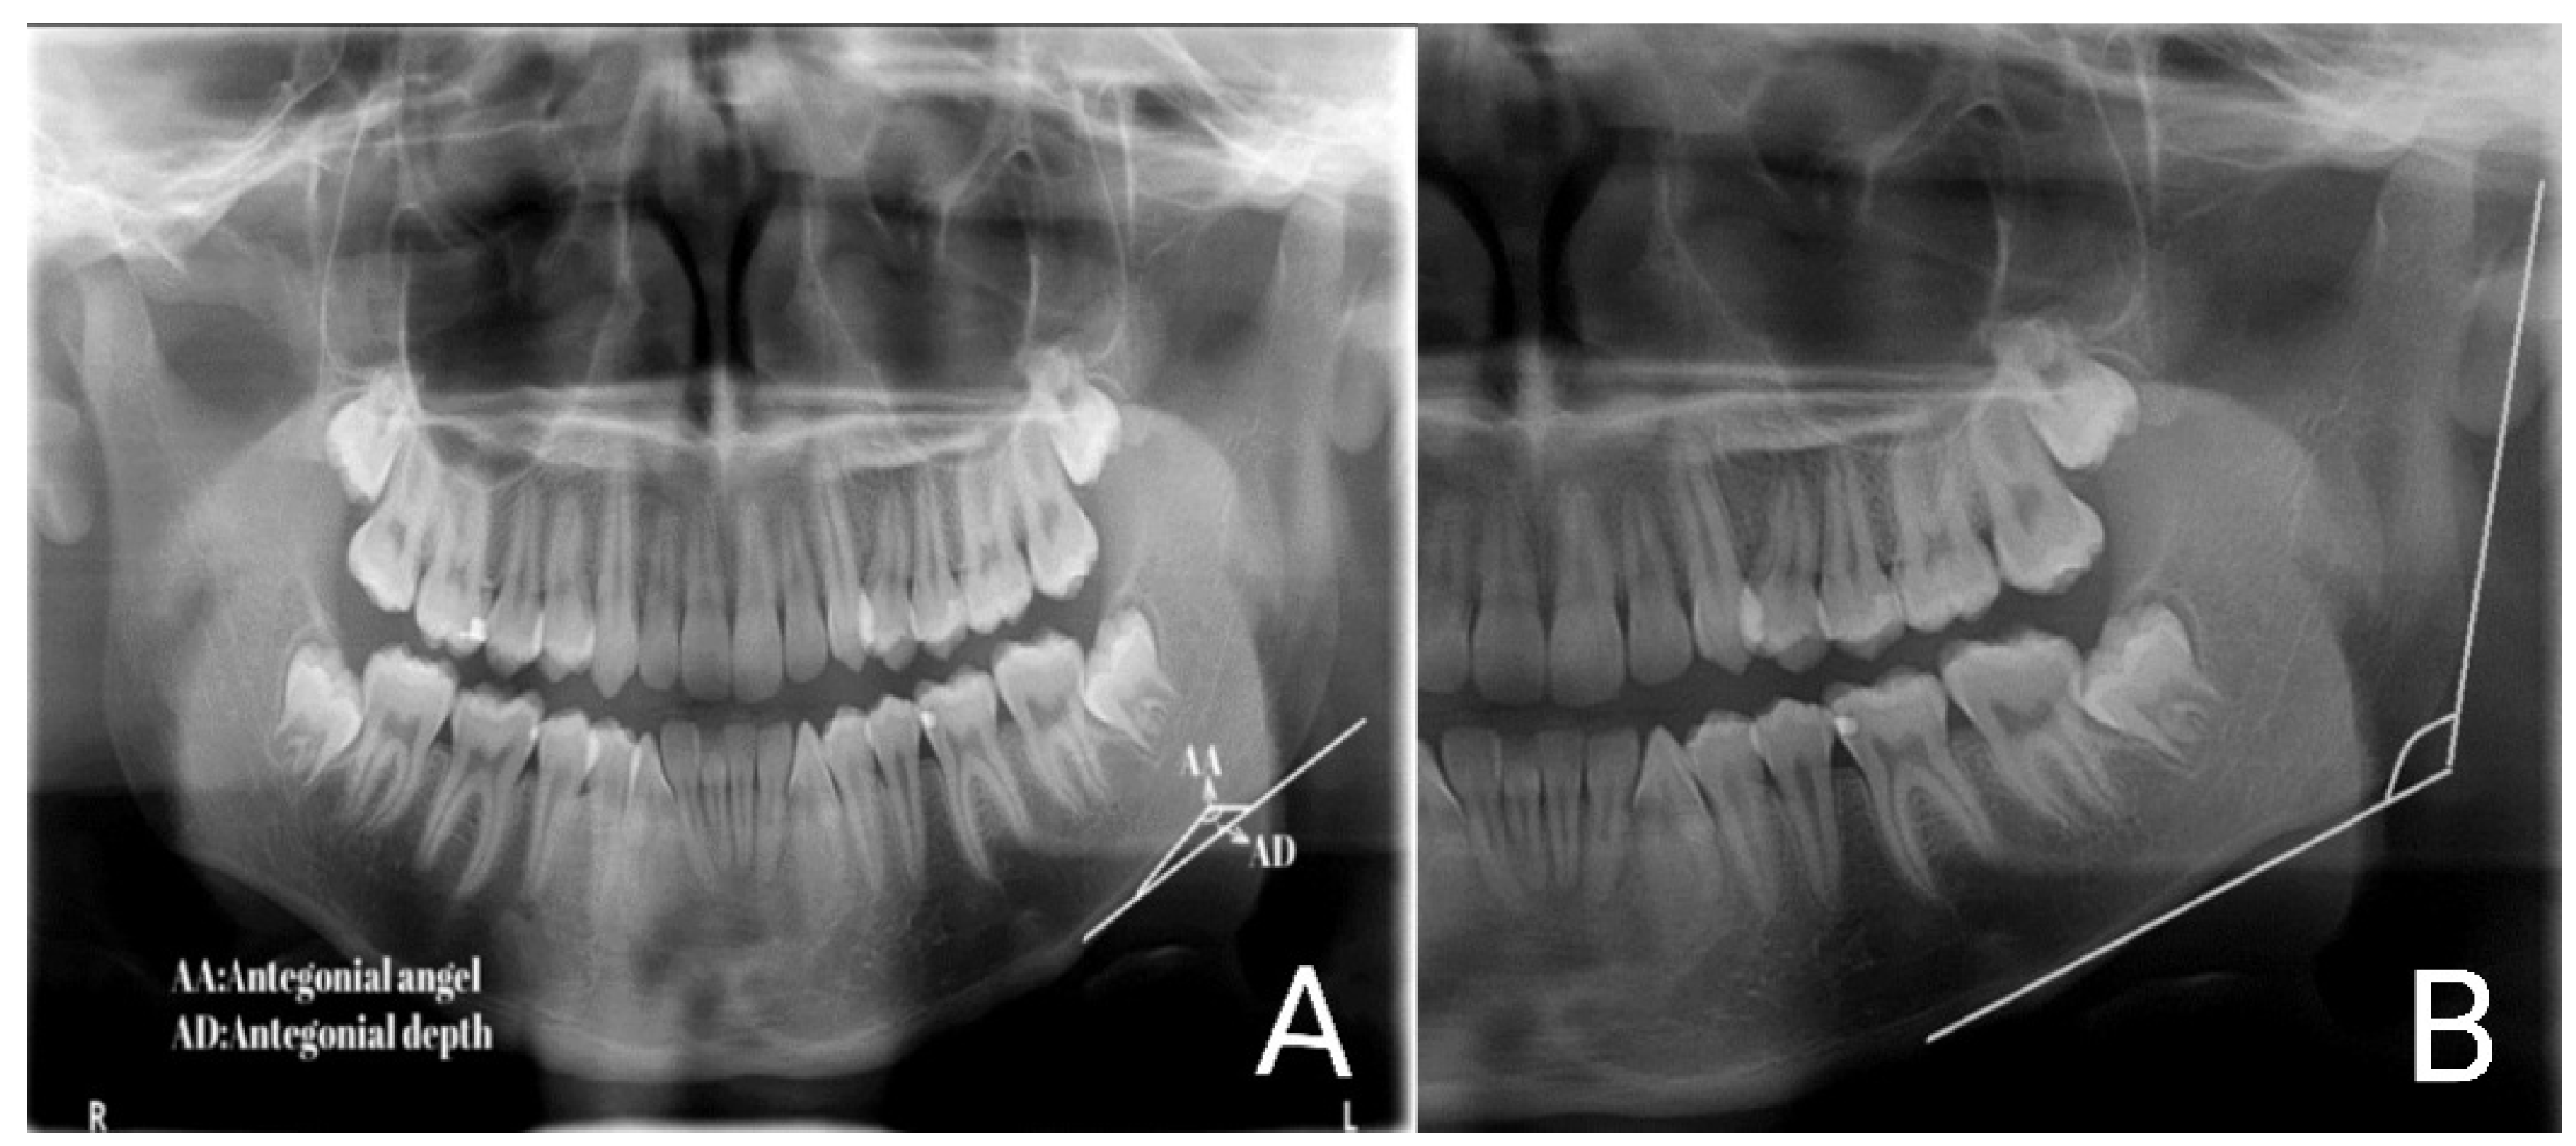

- Tidke, P.; Kulkarni, S.; Agrawal, V.; Saxena, U.; Pandharipande, R. Tooth coronal index (TCI), antegonial angle, and antegonial depth measurement for age estimation using digital panoramic radiograph. J. Indian. Acad. Oral. Med. Radiol. 2019, 31, 353–358. [Google Scholar] [CrossRef]

| Right antegonial angle (degrees) | 162.18 | 6.23 | 148.00 | 178.00 |

| Left antegonial angle (degrees) | 159.66 | 8.24 | 128.00 | 180.00 |

| Mean right and left antegonial angles | 160.92 | 5.79 | 148.50 | 175.00 |

| Right antegonial notch depth (mm) | 1.79 | 0.71 | 0.19 | 4.09 |

| Left antegonial notch depth (mm) | 1.68 | 0.66 | 0.03 | 3.89 |

| Mean depth of the right and left antegonial angles | 1.73 | 0.63 | 0.26 | 3.99 |